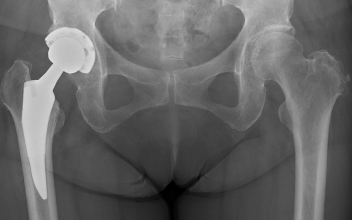

- 人工股関節置換術

当院では、侵襲の少ない前側方アプローチを採用しています。従来の後方アプローチに比べ、術後脱臼のリスクが低く、正座やしゃがみ込みといった日常動作の制限が不要なため、患者さんの生活の質向上に大きなメリットがあります。

術後は約2週間で自宅退院が可能で、3か月以降にはゴルフ・ダンス・テニス・卓球・水泳など多くの趣味やスポーツを再開できます。

人工股関節置換術後レントゲン

人工股関節置換術は執刀する医師や施設によって入院期間やアプローチ(股関節へどの方向から進入するか)、手術時間などにばらつきが大きいのが現状です。当センターでは筋肉を切らずに温存する「前側方アプローチ」を採用しています。従来はお尻の後ろ側からアプローチする方法が一般的でしたが、筋肉を切離するため、術後股関節がゆるくなり、脱臼が一定の頻度で生じていました。これに対して、筋肉を温存する「前側方アプローチ」は脱臼リスクが非常に低いため、正座やしゃがみ込みといった日常動作に制限がないという大きな利点があります。また従来の方法より術後回復が早いという特徴もあります。当院での手術は、平均1時間程度で出血量は200mlほど、約9割の方は輸血を必要としません。手術翌日からリハビリを開始し、通常は2週間ほどで退院されています。

人工股関節置換術 術後レントゲン